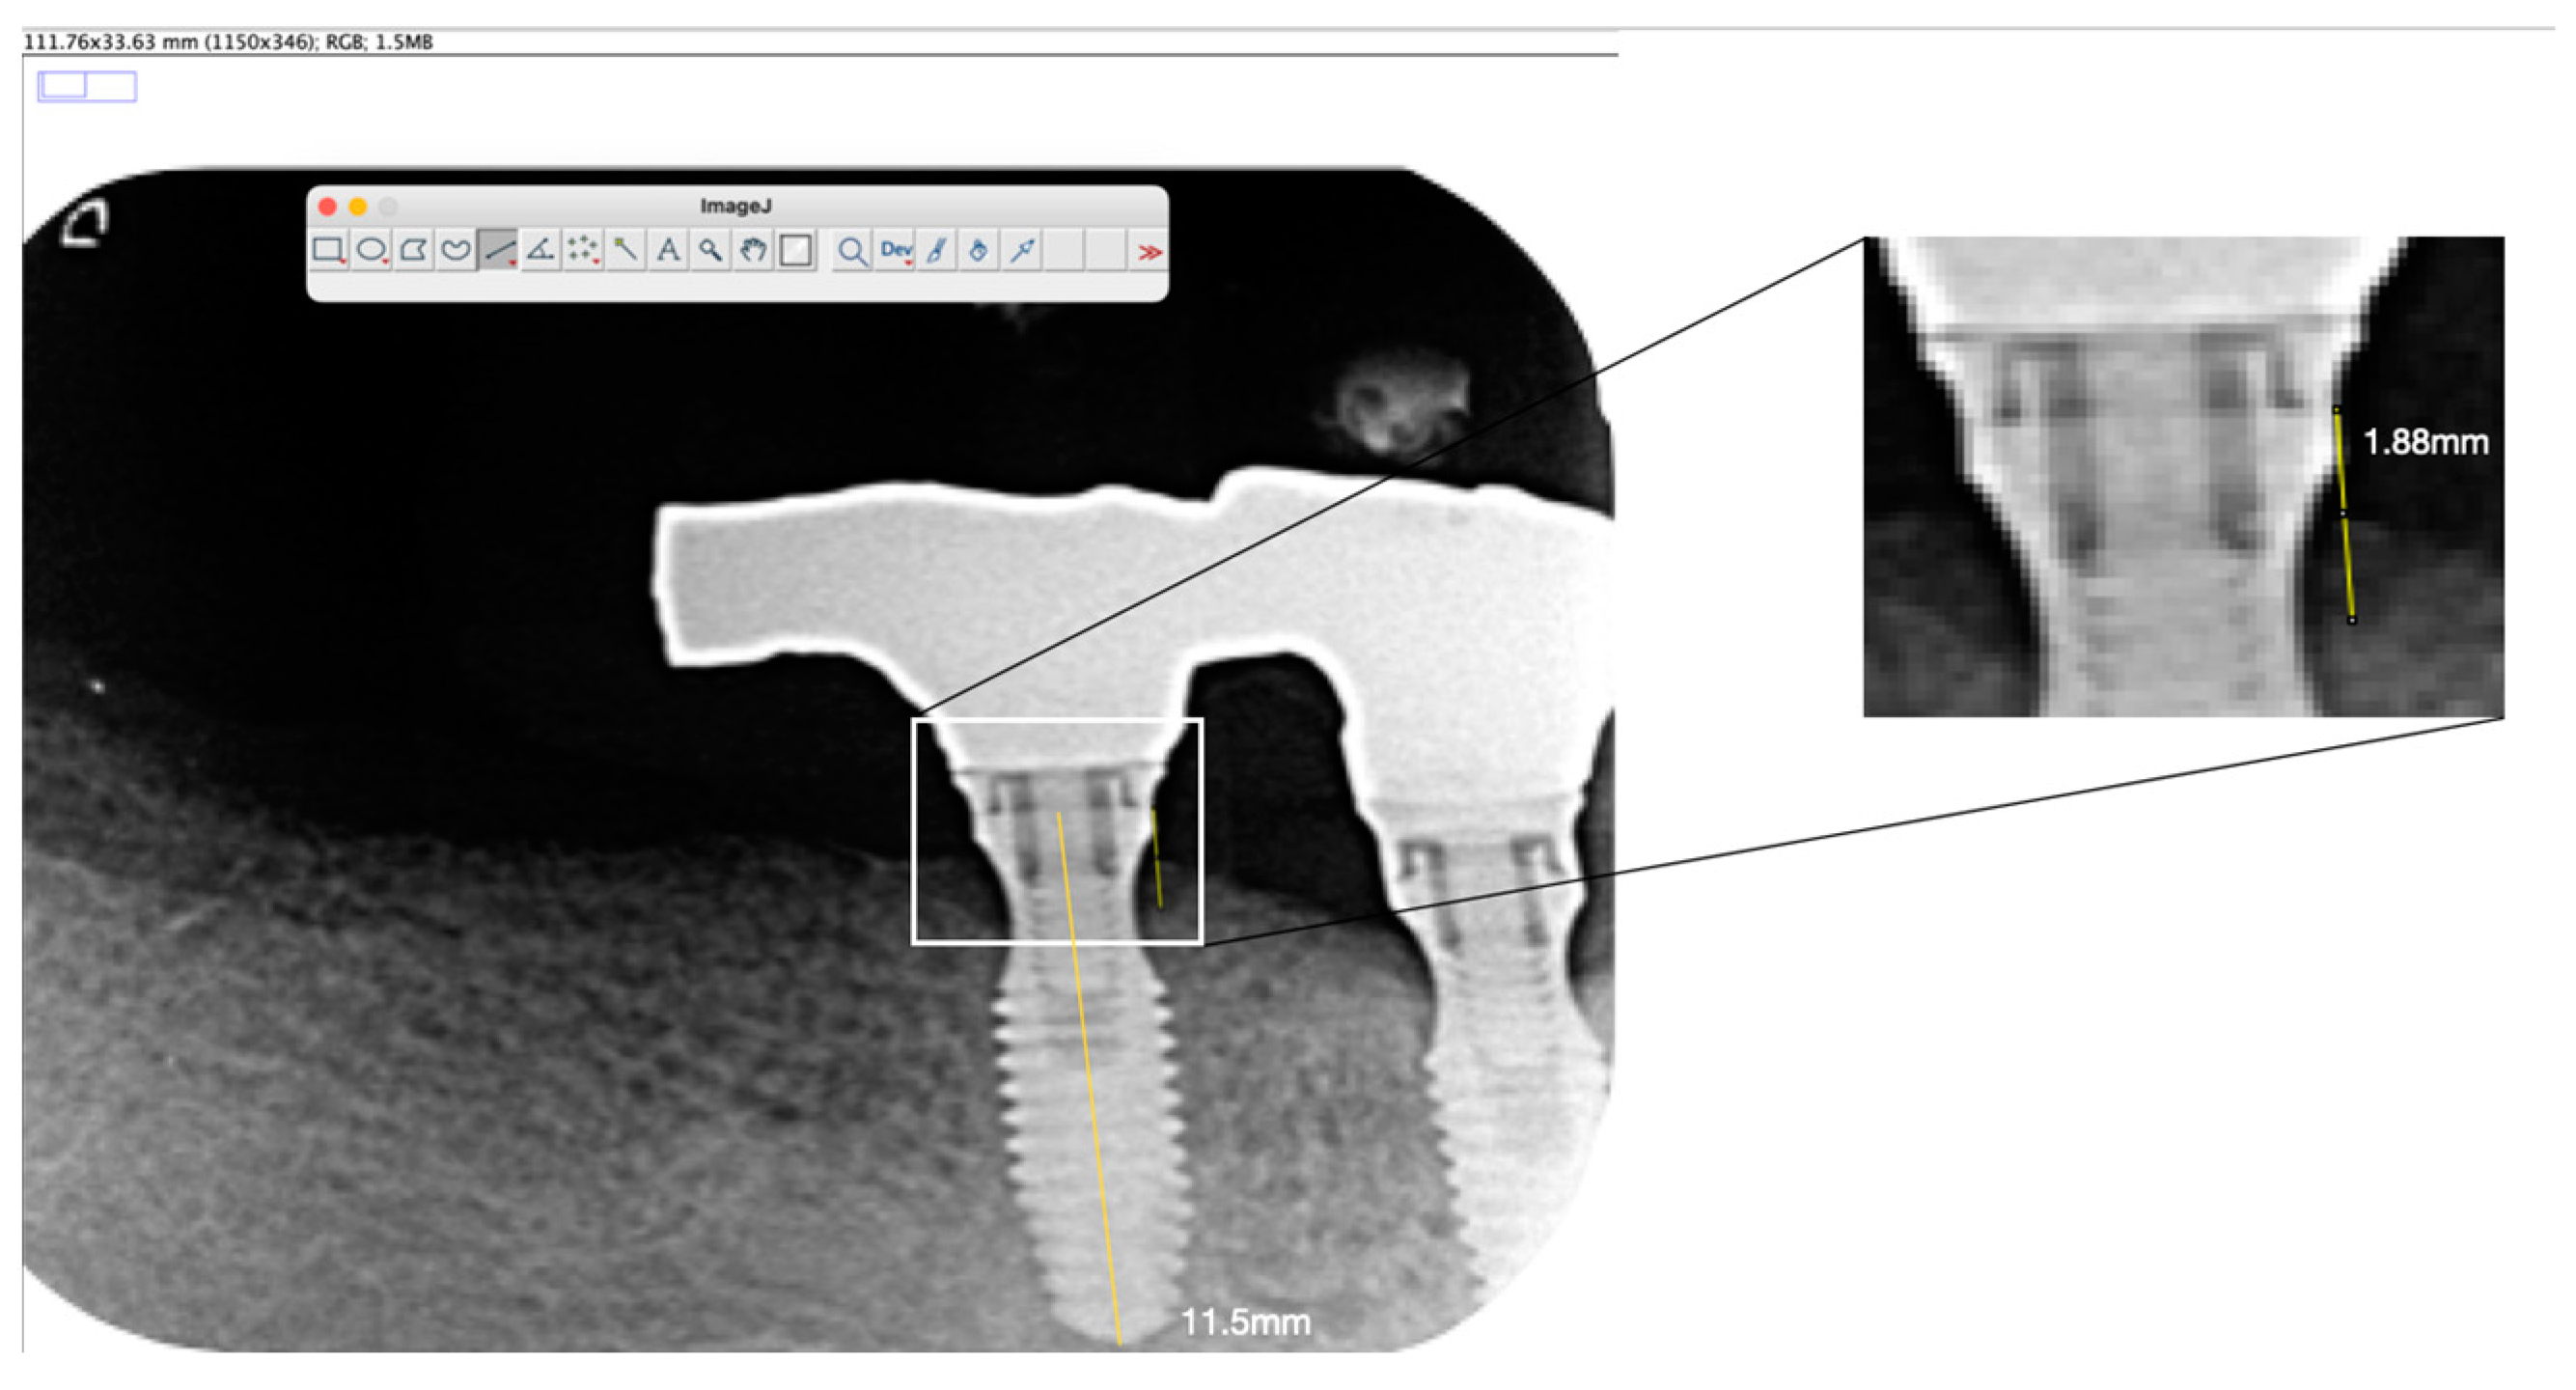

2.4. Radiographic Assessment and Marginal Bone Level (MBL) Measurements

| Case No. | Tooth No. | Initial MBL (mm) | MBL 6 Months (mm) | MBL 12 Months (mm) | KM 6 Months (mm) | KM 12 Months (mm) |

|---|---|---|---|---|---|---|

| 1 | 25 | 0.12 | 2.51 | 2.73 | 3 | 3 |

| 1 | 23 | 0 | 1.85 | 2.73 | 4 | 4 |

| 1 | 22 | 0.08 | 0.21 | 0.37 | 3 | 3 |

| 1 | 12 | 0.32 | 0.33 | 0.36 | 3 | 3 |

| 1 | 13 | 0 | 0.37 | 0.53 | 4 | 4 |

| 1 | 15 | 0.12 | 2.09 | 2.34 | 4 | 4 |

| Mean | 0.06 | 1.23 | 1.51 | 3.5 | 3.5 | |